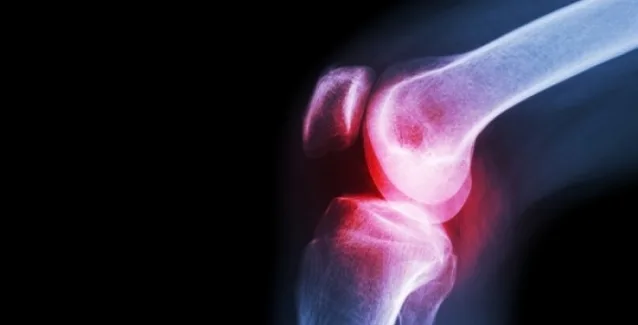

Όταν υπάρχει φλεγμονή στις αρθρώσεις, με αποτέλεσμα αυτές να σκληραίνουν και να πρήζονται, ο πόνος μπορεί να γίνει πραγματικά ανυπόφορος. Υπολογίζεται ότι 1 στους 5 ενήλικες αντιμετωπίζει κάποια από τις περίπου 100 ιατρικές παθήσεις που επηρεάζουν το μυοσκελετικό σύστημα και ειδικά τις αρθρώσεις, όπου συναντώνται δύο ή περισσότερα οστά. Και ενώ ο πόνος στις αρθρώσεις […]

Όταν υπάρχει φλεγμονή στις αρθρώσεις, με αποτέλεσμα αυτές να σκληραίνουν και να πρήζονται, ο πόνος μπορεί να γίνει πραγματικά ανυπόφορος.

Υπολογίζεται ότι 1 στους 5 ενήλικες αντιμετωπίζει κάποια από τις περίπου 100 ιατρικές παθήσεις που επηρεάζουν το μυοσκελετικό σύστημα και ειδικά τις αρθρώσεις, όπου συναντώνται δύο ή περισσότερα οστά.

Και ενώ ο πόνος στις αρθρώσεις δεν εξαφανίζεται για πάντα, προσαρμόζοντας τη διατροφή σας, βοηθάτε το σώμα σας να αντιμετωπίσει καλύτερα τις αρθρίτιδες.